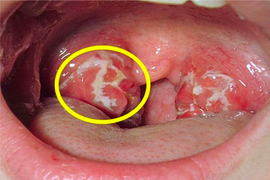

Ung thư vòm họng là căn bệnh vô cùng nguy hiểm nhưng dấu hiệu nhận biết thường dễ nhầm lẫn với các bệnh lý khác.

Đây là những triệu chứng điển hình của bệnh ung thư vòm họng, nếu nghi ngờ, bạn cần phải đi khám càng sớm càng tốt.

Ung thư vòm họng là loại ung thư phổ biến và nguy hiểm bởi triệu chứng âm thầm nhưng tiến triển nhanh, thường phát hiện ở giai đoạn muộn.

Dấu hiệu ung thư vòm họng ở giai đoạn sớm khá kín đáo như nhức đầu, ù tai, ngạt mũi nên bệnh dễ bị nhầm với các triệu chứng của viêm nhiễm vùng tai mũi họng.